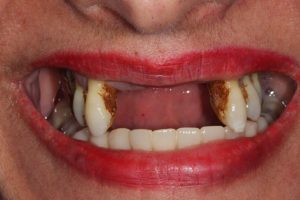

Trauma to Upper Front Teeth

Both central incisors were broken, leaving just the roots. Unfortunately, there wasn’t enough tooth to repair these teeth and they were subsequently removed. Dental implants were placed to restore the missing teeth.